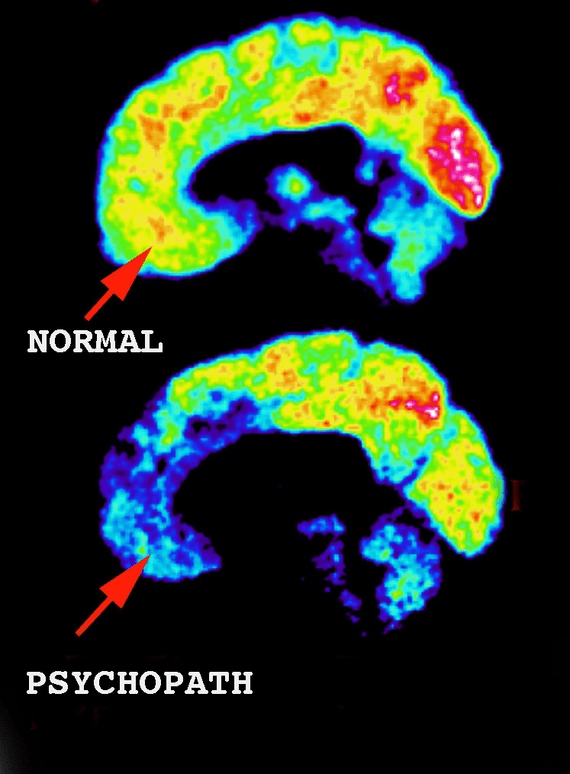

Aunque ven su comportamiento como una señal de que están más altamente evolucionados, la investigación médica muestra que los lóbulos frontales en el cerebro de los psicópatas están casi desactivados.

Esto significa que una parte completa de su neurofisiología que está construida para sentir empatía, compasión y preocupación por los demás simplemente no está funcionando.